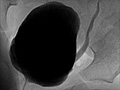

A cystourethrogram is an X-ray test that takes pictures of your bladder and urethra while your bladder is full and while you are urinating. A thin flexible tube (urinary catheter) is inserted through your urethra into your bladder. A liquid material that shows up well on an X-ray picture (contrast material) is injected into your bladder through the catheter, then X-rays are taken with the contrast material in your bladder. More X-rays may be taken while urine flows out of your bladder, in which case the test is called a voiding cystourethrogram (VCUG).

A cystourethrogram is an X-ray test that takes pictures of your bladder and urethra while you are urinating. Some results may be available immediately after the cystourethrogram. Final results are usually available within 1 to 2 days.

Normal:

The bladder appears normal.

Urine flows normally from the bladder.

The bladder empties all the way.

The contrast material flows evenly out of the bladder through a smooth-walled urethra.